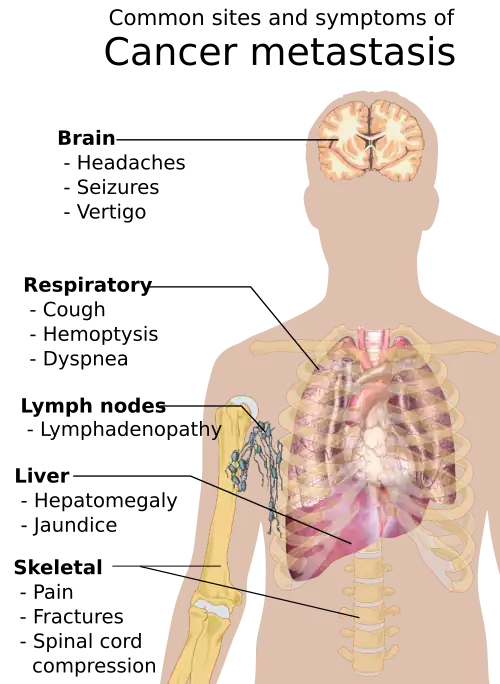

Symptoms of cancer metastasis depend on the location of the tumor.

Metastasis is the spread of cancer to other locations in the body. The dispersed tumors are called metastatic tumors, while the original is called the primary tumor. Almost all cancers can metastasize.[40] Most cancer deaths are due to cancer that has metastasized.[41]

Different types of cancers tend to metastasize to particular organs. Overall, the most common places for metastases to occur are the lungs, liver, brain, and the bones.[40]